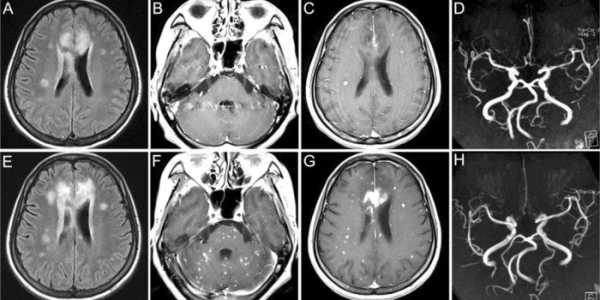

Біллі Мілліган не єдина людина, яка мала розлад ідентичності. 33-річна пацієнтка німецької клініки за 13 років до потрапляння до лікарні втратила зір. Сліпота настала після аварії. Підставою для звернення став дисоціативний розлад особистості — в пацієнтки було більше десяти особистостей, що відрізнялися за віком, статтю та рисами характеру. В процесі лікування одна з її особистостей, юнак-підліток, почала бачити, а потім стали бачити практично всі інші особистості, за винятком двох. Дослідження енцефалографом довело, що пацієнтка говорить правду — коли поточна особа була сліпою, мозок не проявляв електричної активності на візуальні стимули.